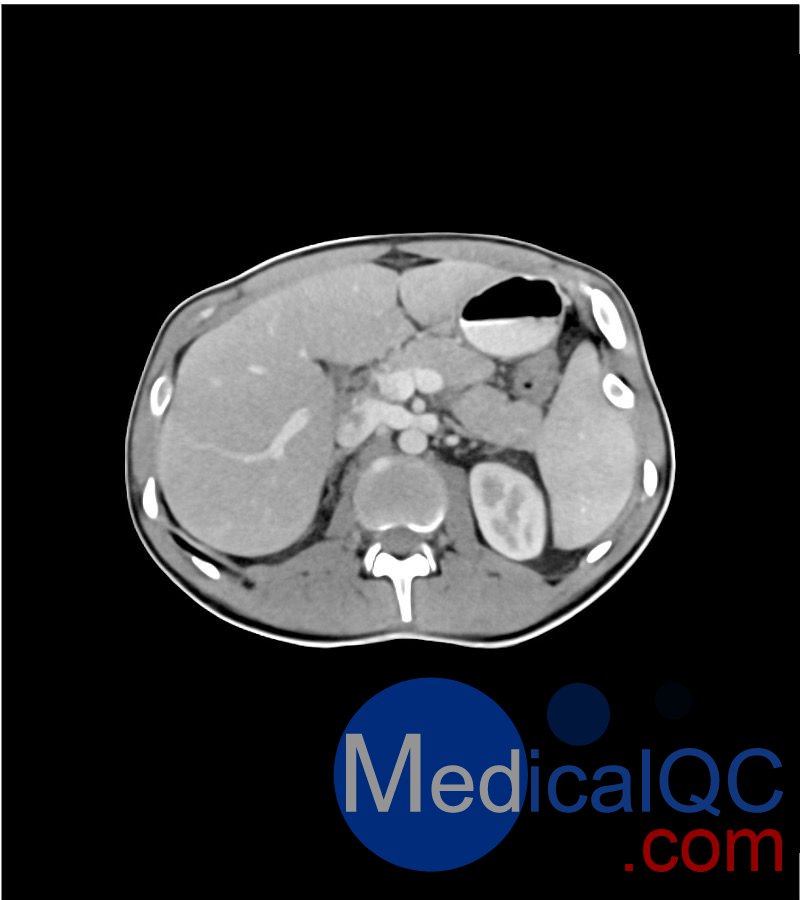

WEK-5501男性腹部模體,WEK-5501男性骨盤模體可模擬門靜脈期的腹部和盆腔增強掃描效果,掃描范圍覆蓋第一腰椎至?xí)巺^(qū)域。

該體模右側(cè)設(shè)有髂淋巴結(jié)腫塊(模擬病灶)。

1. 可對脈管系統(tǒng)、骨骼及軟組織進行逼真模擬,涵蓋的器官包括肝臟、膽囊、胰腺、脾臟、腎上腺、腎臟、胃、小腸、結(jié)腸、膀胱及前列腺。

WEK-5501男性腹部模體,WEK-5501男性骨盤模體成像效果圖: